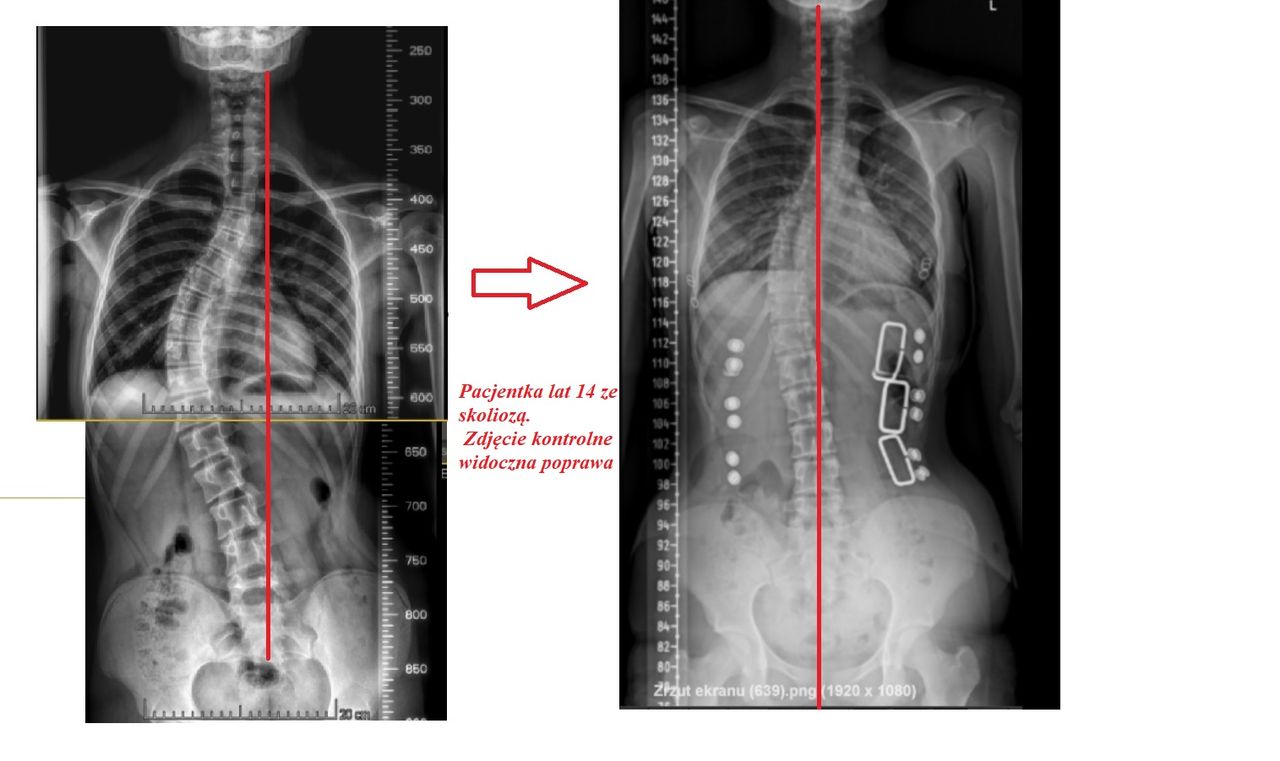

- Skolioza

Wizualna korekcja jest możliwa nawet i u starszych osób. Wszystko zależy od rodzaju i stopnia skoliozy. Odpowiednio dobrana terapia nie tylko poprawia komfort życia niwelując ból ale wpływa , na układ krążenia czy właśnie na wizualny aspekt postawy ciała.